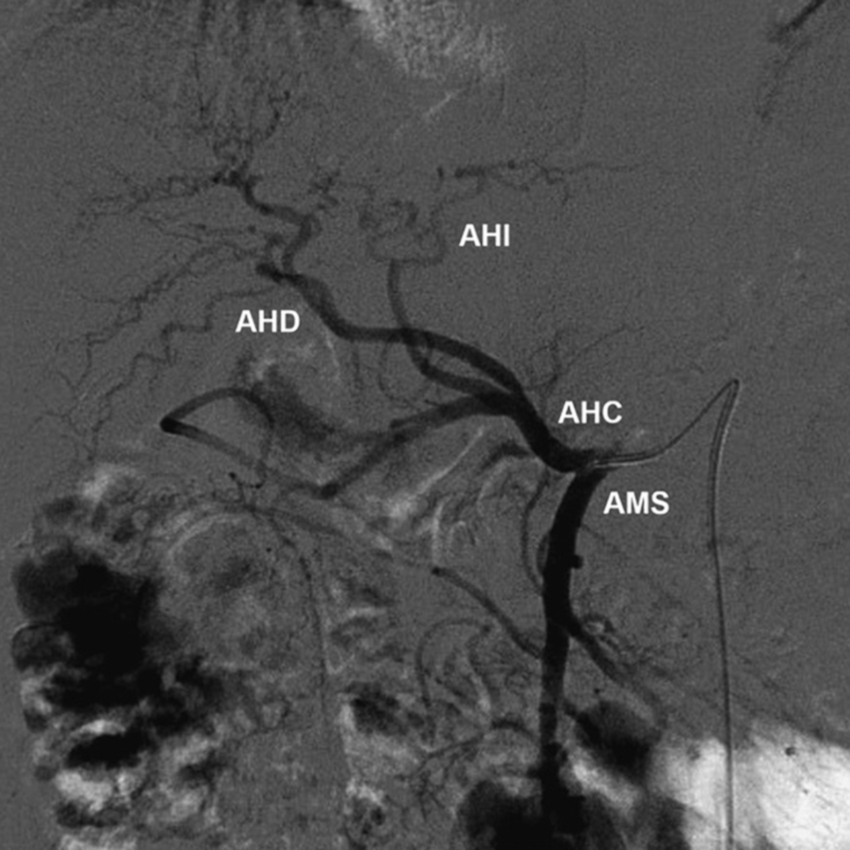

La AHP recorre hacia la derecha y por encima del borde anterior del foramen epiploico y a nivel del hilio hepático se bifurca en la arteria hepática derecha (AHD) y la arteria hepática izquierda (AHI). Estas ramas terminales hepáticas penetran el porta hepático, por delante de la rama de la vena porta hepática correspondiente, y se distribuyen siguiendo las ramificaciones venosas portales intrahepáticas de la segmentación de Couinaud10,13. En la presentación anatómica clásica, la AHI se extiende hacia la base de la fisura umbilical y desprende ramas hacia el lóbulo caudado o segmento I y los segmentos II (A2) y III (A3). El lóbulo caudado está irrigado por ramas de pequeño calibre de la AHD (35%), de la AHI (12%) o de ambas (53%)5 (Fig. 2). La AGI infrecuentemente puede dar una AHI aberrante o accesoria5,13.

La AHD suele pasar por detrás del conducto hepático común y típicamente se divide en una rama anterior y otra posterior. La rama anterior se dirige hacia los segmentos V y VIII (A5 y A8), y la rama posterior hacia los segmentos VI y VII (A6 y A7).

Tipo 1: AHD y AHI con origen en la AHC (Fig. 4).